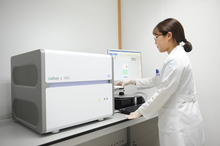

양산부산대병원, 혈액으로 비소세포폐암 암유전자 진단 12월 시작